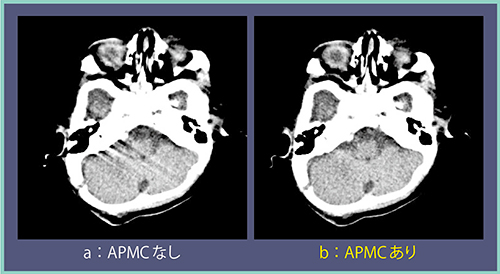

図5も0.5秒で撮影した生後4か月の小児の頭部画像だが,体動があり,低月齢のためコントラストも付かないものの,出血や骨折などの大きな変化はないことがわかる。また,1ボリューム撮影のメリットとして,体動補正の“Advanced Patient Motion Correction(APMC)”を使用できることが挙げられる。ノイズは多少増加するが,APMCによってアーチファクトを除去した画像が作成可能である(図5 b)。

図5 エリアファインダを用いた小児頭部撮影とAPMCの効果(生後4か月)